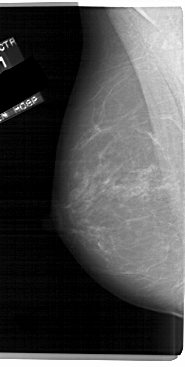

A_1694_1.LEFT_MLO

LEFT_MLO LINES 5491 PIXELS_PER_LINE 2761 BITS_PER_PIXEL 12 RESOLUTION 43.5 NON_OVERLAY